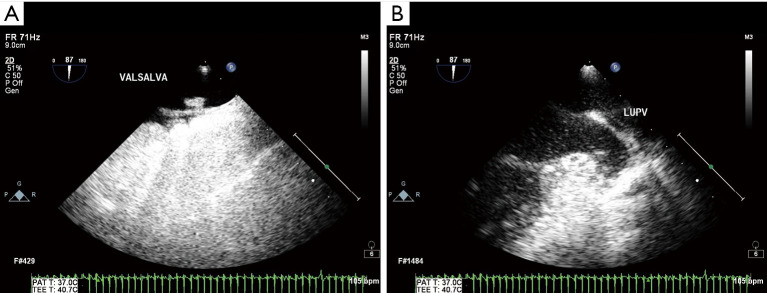

Methods: A total of 117 patients diagnosed with CS from October 2020 to June 2024 were randomly collected, and 93 patients with only headache and dizziness were randomly collected as the control group. All patients underwent agitated saline contrast echocardiography (ASCE) and the semi-quantitative classification, type and duration of RLS were analyzed. Spearman correlation analysis was used to analyze the correlation between RLS grade and type and the occurrence of CS, and the correlation between RLS duration and RLS grade and type. The efficacy of different RLS grades, types and durations in the diagnosis of CS were analyzed by receiver operating characteristic (ROC) curve.

Abstract Image